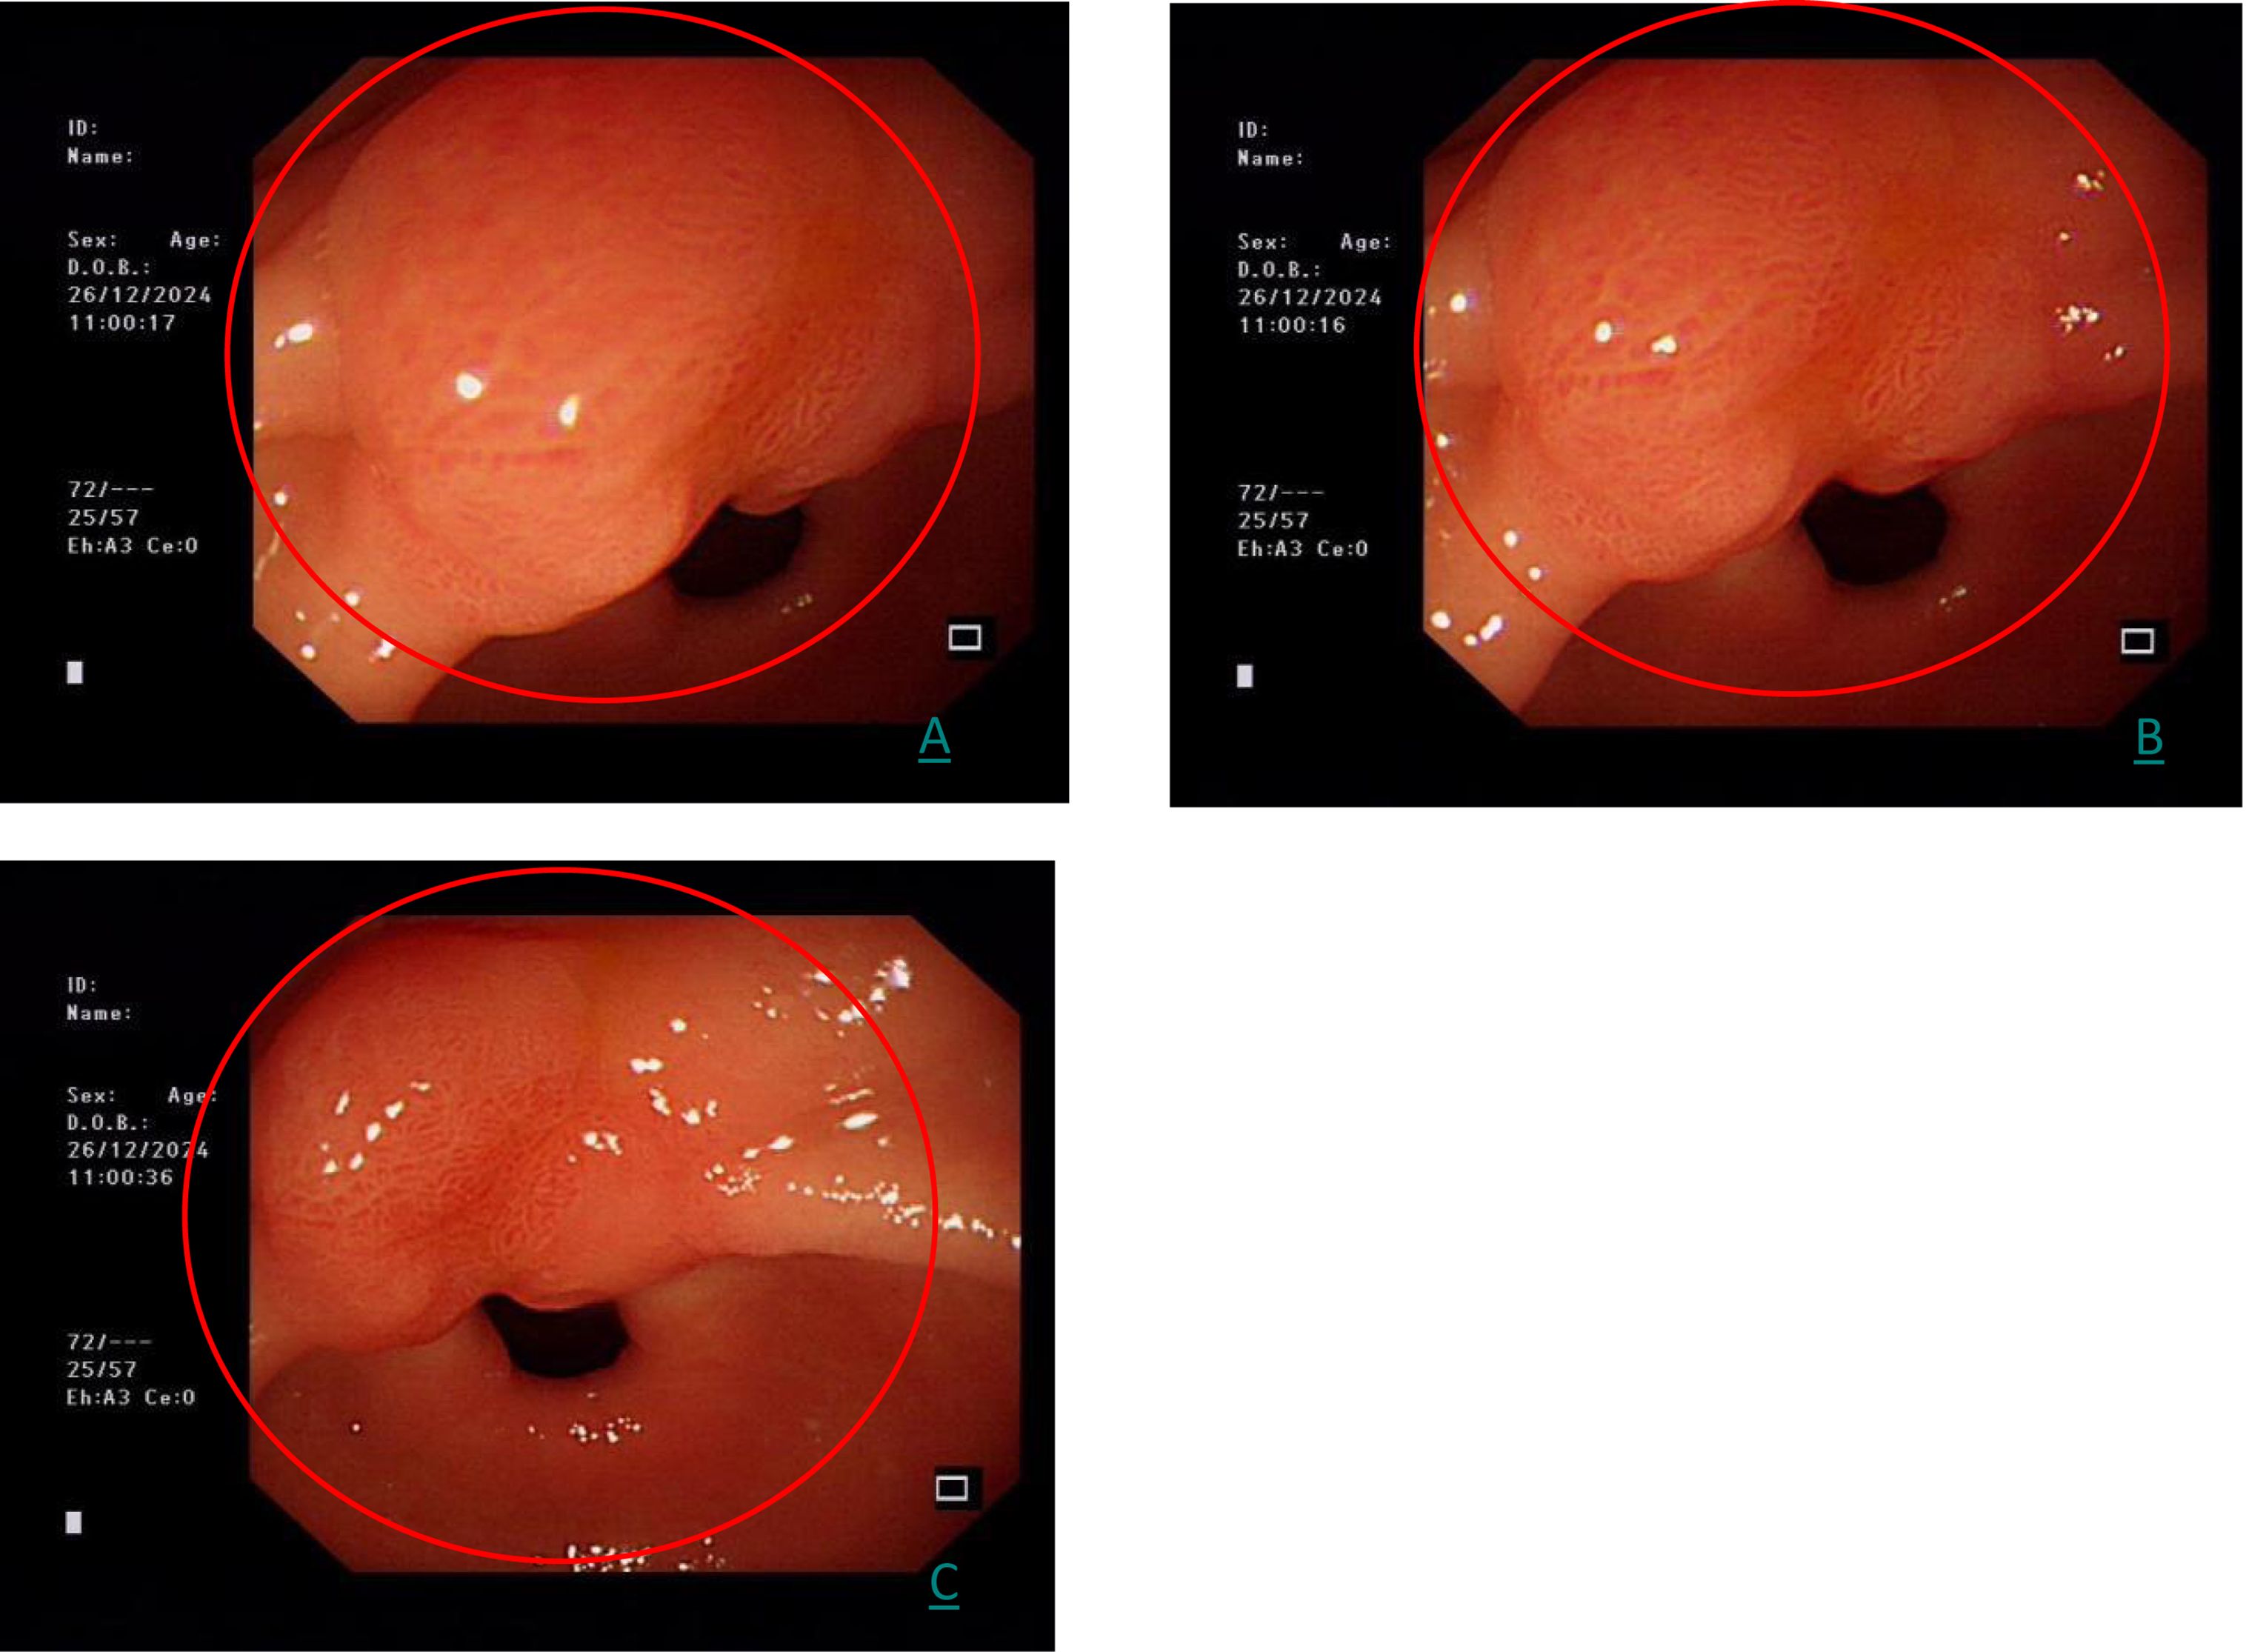

A follow-up gastroscopy on December 26, 2024 showed the same lesion, which is consistent with the initial examination (Figure 2).

Figure 2. (A–C) represents the three images of the same gastric antrum lesion at different angles by white light endoscopy (red circle).